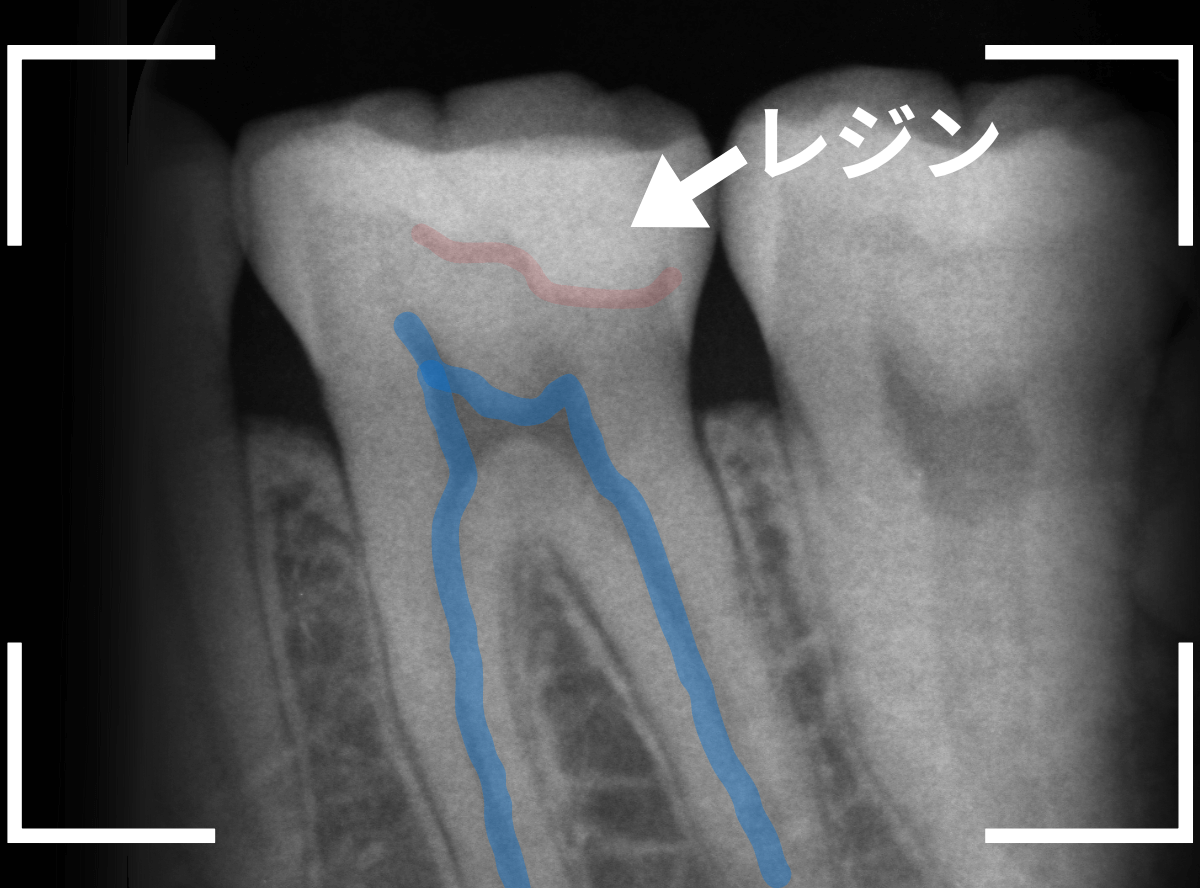

レントゲン写真で確認します。

赤い線がレジンが入っている部分。

青い線が歯の神経です。

かなり神経の近いところまでレジンがつめてあるのがわかりますが、虫歯が側面からどの程度進んでいるのかはよくわかりません。

レントゲン写真だけみると、治療の必要がなさそうにも見えます。

このように、初見では虫歯になっている事が明らかなのに、レントゲン写真ではまったくわからないとう事もあります。